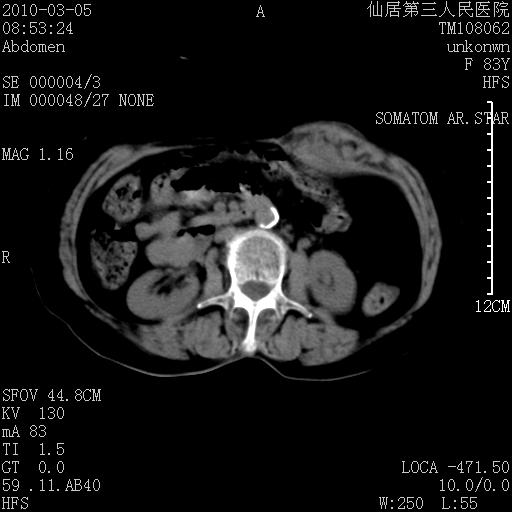

标题: CT24879:腹直肌病变。在线等。

女性,83y,腹痛一周。

考虑:左侧腹直肌神经纤维瘤可能

神经纤维瘤—伴有出血?

有无外伤,血肿或韧带样瘤

增强看看,mfh可能性大,次之可考虑血肿、bfh、转移瘤、神经纤维瘤、侵袭性韧带样纤维瘤等。肝内钙化灶,右肾结石。